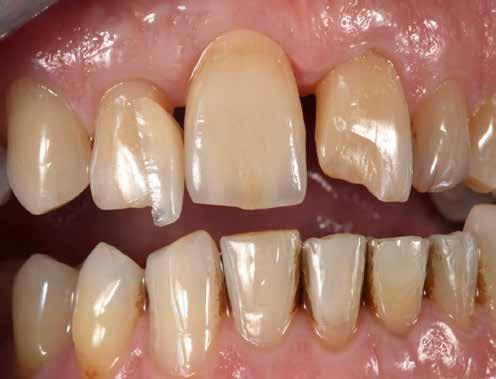

A pácienseset

Ötvenéves hölgy elégedetlen volt felső frontfogai esztétikai megjelenésével. Ezért elment a rendelőbe. Klinikailag vesztibulárisan két nagy kompozittömés volt megfigyelhető, széli elszíneződéssel. Az élek lefutása egyenetlen, aszimmetrikus volt. A frontfogakon recessziók és a nyakak szabaddá válása volt megfigyelhető. A hölgy a fogív gyors restauratív nivellálását kívánta. A nagymetszők közötti diasztémát csökkenteni kellett, de nem zárni, hogy megmaradhasson az optimális hossz-szélesség arány. A recessziók kötőszöveti fedését műtéttel kizárta. Viaszmintázat és intraorális mock-up segítségével szimuláltuk a teljes kerámiahéjakat, illetve segítettük a minimálinvazív preparációt a zománc területén. A páciens világos színű restaurációt akart. Vázanyagként a felső frontok területén a VITA AMBRIA anyagot terveztük használni, hogy a héjak életteli, színhelyes alapot kapjanak, egyidejűleg elérve az igen magas, 500 MPa-os szilárdságot. Az egyéniesítés megvalósítását VITA LUMEX AC leucit-erősítésű üvegkerámiával terveztük, hogy kevés, szín- és formastabil égetéssel reprodukálhassuk a fogakat. A 23-as szemfogat – palatinálisan megfigyelhető defektusa miatt – egyedüliként teljes koronával terveztük rehabilitálni, ugyanezzel az anyagkombinációval. A bukkális folyosó feltöltése érdekében a premolárisokra is héjak kerültek. Ezek természetes fluoreszcenciájának, transzlucenciájának és opaleszcenciájának eléréséhez monolit VITA AMBRIA munkákat készítettünk, felszíni festéssel.

A kiindulási helyzet recessziókkal és szabálytalan éli lefutással.